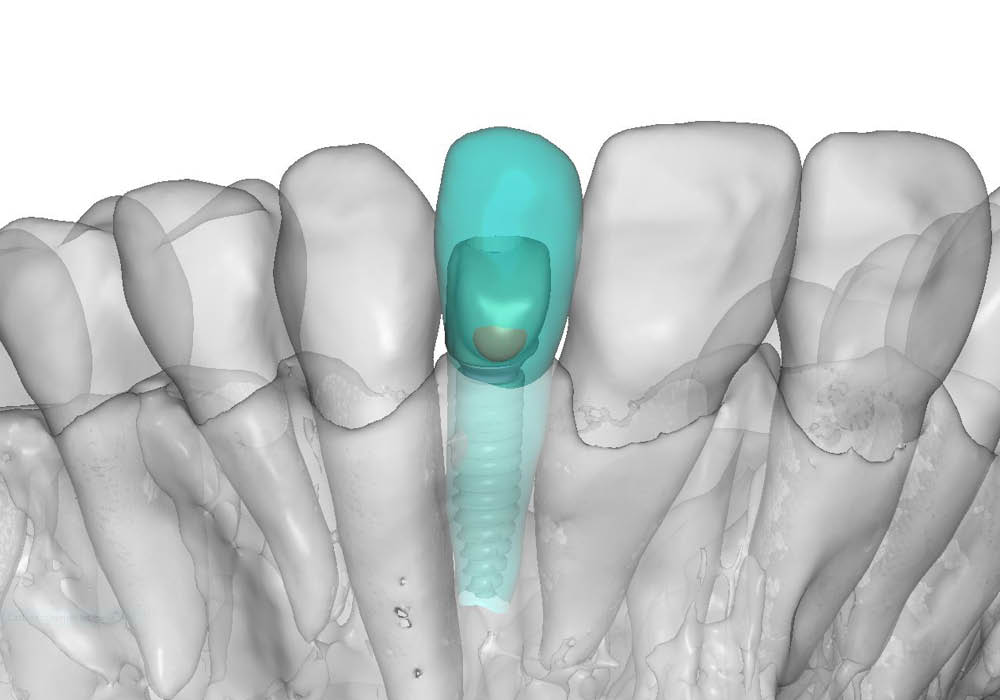

La pianificazione chirurgica ha previsto un’analisi tridimensionale dettagliata del sito implantare, valutato sia da angolazioni multiple sia in visione frontale diretta.

L’obiettivo era quello di definire con precisione posizione, profondità e inclinazione dell’impianto, tenendo conto della vicinanza delle radici adiacenti e della necessità di preservare un adeguato spessore vestibolare.

Questa fase ha permesso di anticipare eventuali criticità e assicurare l’inserzione corretta all’interno dei limiti anatomici disponibili.

5. Costruzione del tappo di guarigione in PEEK

Su misura per la paziente, è stato realizzato un tappo di guarigione anatomico in PEEK, progettato per guidare correttamente la guarigione dei tessuti molli e mantenere il profilo di emergenza ideale in funzione del futuro restauro.